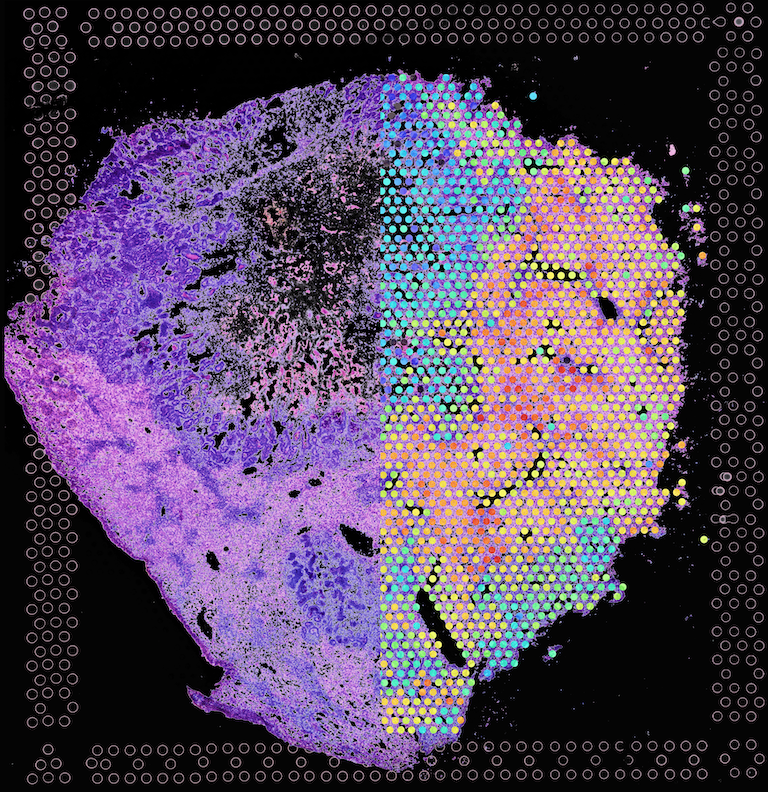

The image shows a hematoxalin and eosin stained metastatic colon cancer as it invades and grows in the liver on the left. On the right it shows spatial transcriptomics, or what “programs” or instructions that each of the cells are carrying out at the time we took this section. The hexagonal cells are the areas which we performed analysis using a new technology called spatial transcriptomics. We found a few genes which highlight the tumor cells in comparison to the surrounding liver tissue. We wanted to use our advanced tumor models using organoids, with spatial transcriptomics to find gene expression signatures that are associated with invasive and growing tumors.